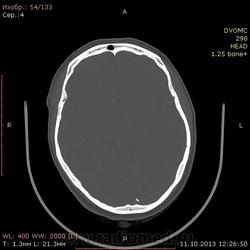

42 года. Слева в лобной доле кровоизлияние в 2011 году. Это понятно.

Есть другой вопрос нормальное ли обызвествление в затылочной доле?

Может обызвествление твердой мозговой облочки.

Стоит ли судить о какой-то динамике имея только предыдущие КТ-снимки?

Ну, если предыдущие снимки есть, можно попытаться.